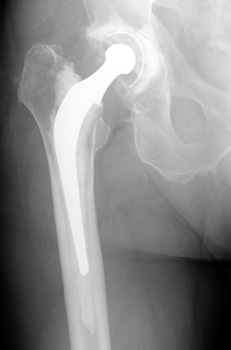

Arthroplasty Fixation

Cement

Porous coating

Press-fit

- Especially useful in patients with osteoporosis

- Cemented acetabular components have progressively increased rate of loosening

over time, thus hybrid total hip replacement (cementless acetabular component

with cemented femoral component) are frequently performed

- Surface coating of metal, ceramic, or polymers, or combination.

- Formed into beads, irregular particles, or etchings

- Allows for bone ingrowth

Porous coated acetabular cup and proximal femoral components,

polyethylene cup liner

Press fit

- Acetabulum and femur prepared for maximum, optimal fit

- Technically demanding surgery

- Acetabular component frequently secured with screws

- Femoral component may fit tightly, but may not fill canal in all planes